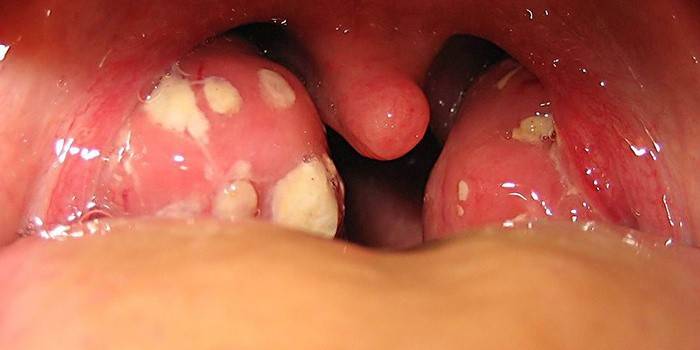

Uma doença chamada amigdalite é caracterizada por um processo inflamatório das amígdalas. As causas da doença são consideradas um vírus ou bactéria patogênica. A maioria das pessoas de sua própria experiência sabe como são os sinais de uma dor de garganta e quais complicações ela leva. Na foto você pode ver como a garganta fica com angina. Considere os fatores característicos de uma doença viral, na presença dos quais voltam ao terapeuta e começam o tratamento.

A causa da amigdalite purulenta é considerada micróbios, por exemplo, estreptococos. A inflamação aparece pela primeira vez nas amígdalas e, em seguida, se a doença não for interrompida no tempo, ela se espalha para a membrana mucosa da faringe, o tecido palatino. Tipo purulento de infecção é dividido em folicular e lacunar.

Folicular

Sintomas de um tipo folicular de doença viral:

- aumento da temperatura corporal (até 40 graus), dura muito tempo e não diminui;

- transpiração, garganta seca, crises de tosse intensa;

- inchaço e vermelhidão das amígdalas, dor de garganta severa;

- sinais de envenenamento, fraqueza, calafrios;

Lacunar

A tonsilite lacunar em crianças se desenvolve rapidamente, em comparação com adolescentes e adultos.A infecção lacunar é muito perigosa para a saúde de um paciente pequeno. Isto é devido a alta temperatura, convulsões, intoxicação grave do corpo. O estágio inicial do mal-estar é caracterizado por sensações dolorosas na garganta, sinais de intoxicação geral. Um pouco mais tarde, os seguintes sintomas gerais de infecção lacunar são observados:

- nas glândulas aparece uma placa com pus.